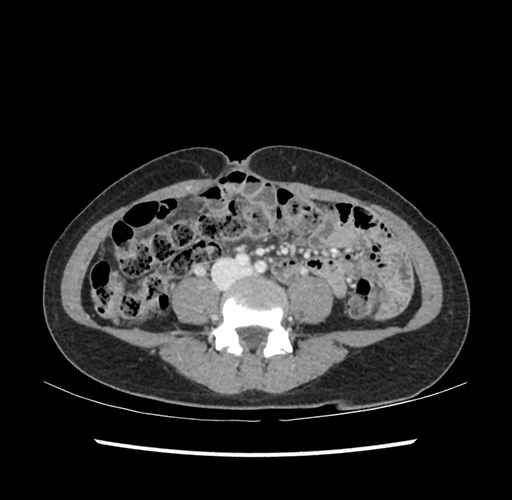

Imaging Analysis

Look through the patient's CT scan to identify any areas of concern for the necessary procedure.

Based on your CT findings, which issue(s) would give reason for "planned slowing down moment(s)" in this case?

Considering a standard left lateral sectionectomy procedure, what step(s) of the operation would you do differently in this case ?